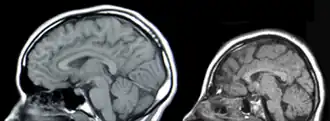

Das GLUT1-Defizit-Syndrom wird autosomal-dominant vererbt. Im Fall der Vererbung hat meist ein Elternteil eine leichte Form des Syndroms. Die Krankheit manifestiert sich neonatal beziehungsweise im Kleinkindalter und wird durch einen Mangel an GLUT1-Transportern im Endothel der Blut-Hirn-Schranke hervorgerufen. Dadurch wird das Gehirn nicht ausreichend mit D-Glucose versorgt und die betroffenen Patienten zeigen unter anderem eine Mikrozephalie, psychomotorische Retardierungen, Ataxie und eine Reihe anderer neurologischer Störungen.[3] Der Phänotyp ist jedoch sehr unterschiedlich und es wurden bisher verschiedene atypische Varianten beschrieben.[4]